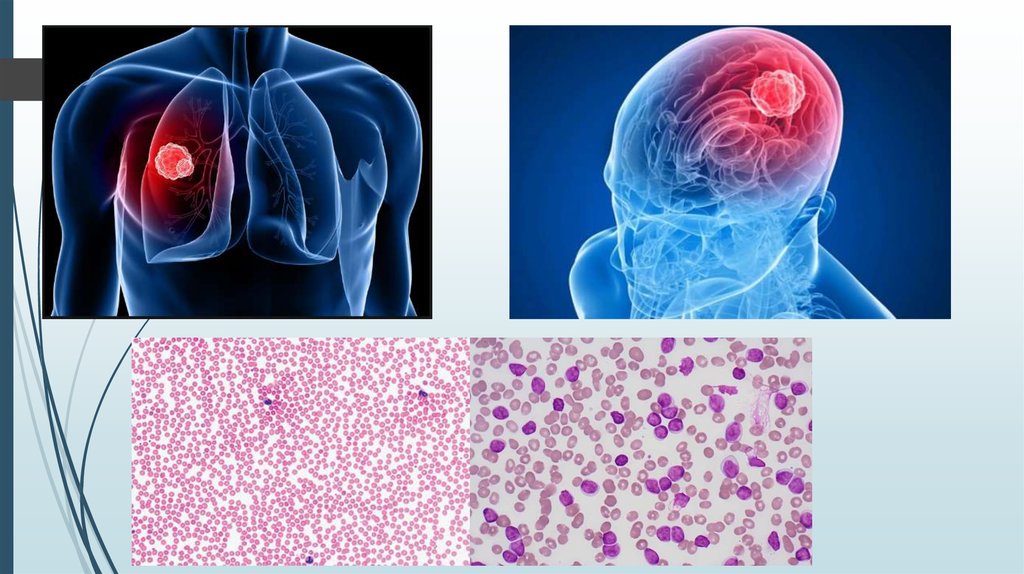

Диагностика ра а желудка. РВК желудка дипгностика. Иагностика рада желудка. Методы диагностики в онкологии. Опкхолльлголовного мозга. Новообразование в головном мозге. Злокачественная опухоль головного мозга.

Опкхолльлголовного мозга. Новообразование в головном мозге. Злокачественная опухоль головного мозга. Методы диагностики опухолей. Метод диагностики опухолей. Методы выявления опухоли. Этапы диагностики опухолей.

Злокачественная опухоль. Злокачественные новообразования. Опухолевые заболевания мозга. Лимома Беркита Тип злокачесивенных клеток. Клетки Березовского-Штернберга морфология. Ходжкинская лимфома морфология. Цитологическая картина лимфомы Ходжкина.

Лимома Беркита Тип злокачесивенных клеток. Клетки Березовского-Штернберга морфология. Ходжкинская лимфома морфология. Цитологическая картина лимфомы Ходжкина. Кт при опухоли надпочечников. Кортикостерома надпочечника кт. МСКТ объемное образование надпочечника. Кт мрт аденома надпочечника.